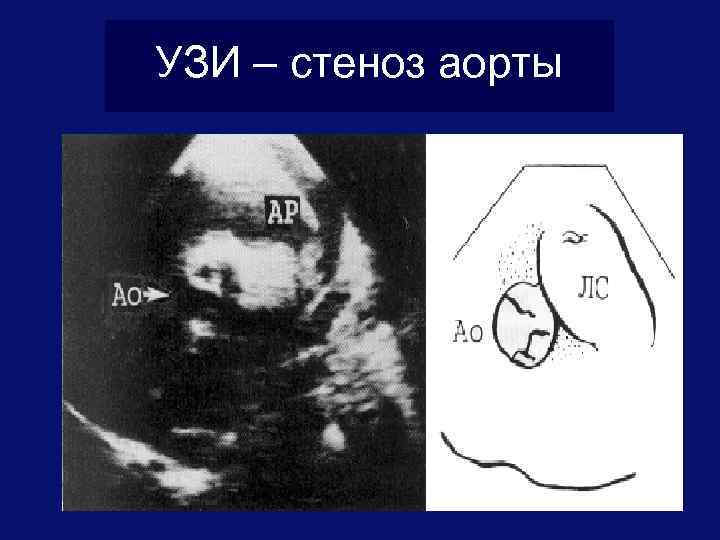

УЗИ – стеноз легочной артерии

УЗИ – стеноз аорты